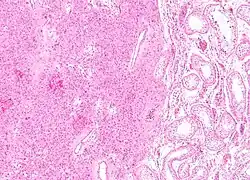

Low magnification micrograph of a Leydig cell tumour. H&E stain.

A conclusive diagnosis is made via histology, as part of a pathology report made during or after surgery. Reinke crystals are classically found in these tumours and help confirm the diagnosis, although they are seen in less than half of all Leydig cell tumours. Immunohistochemical markers of Leydig cell tumours include inhibin-alpha, calretinin, and melan-A.[9]